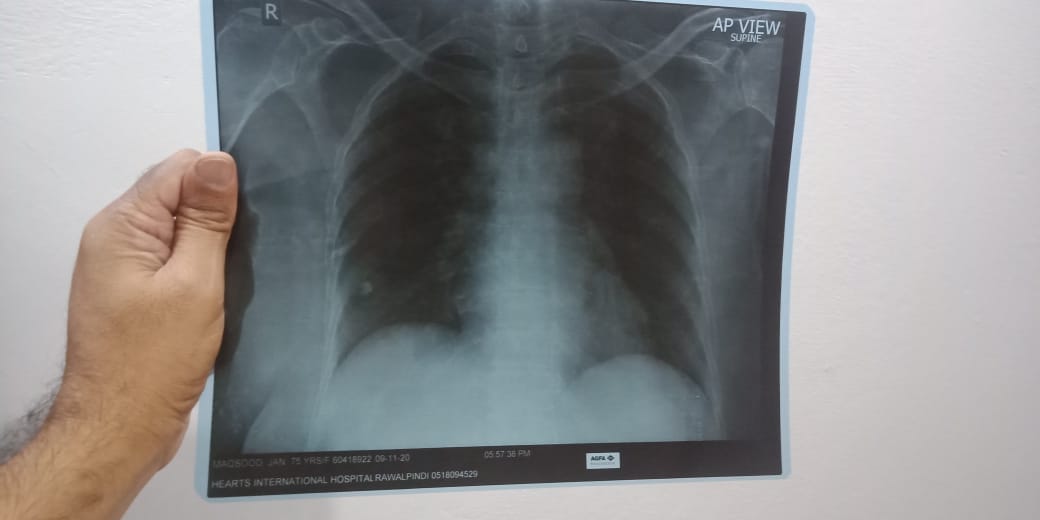

Aoa. It's my mother's 12th day of symptoms. She is Corona positive. M attaching her initial x-ray report. Her oxygen saturation remains 95 plus. Respiratory rate 23/mint. Fever is low grade. I want to know cough syrup for her. Cough her time nai Hoti. Per jab Hoti ha 1 2 mint rehti hai.

plz send xray film

Xray

X-ray film from day 8

It's post Covid fibrosis

Cough keliye Syp bhi Zaruri hai but she would need bronchodilators in the form of

Inhalers regularly and nebulization..

X-ray of day 8

send x-ray films. no need of nebulization if Covid positive. it will not help in fibrotic lung it can help a bronchoconstricted lung to dilate

X-ray from day 8. It's day 13 now